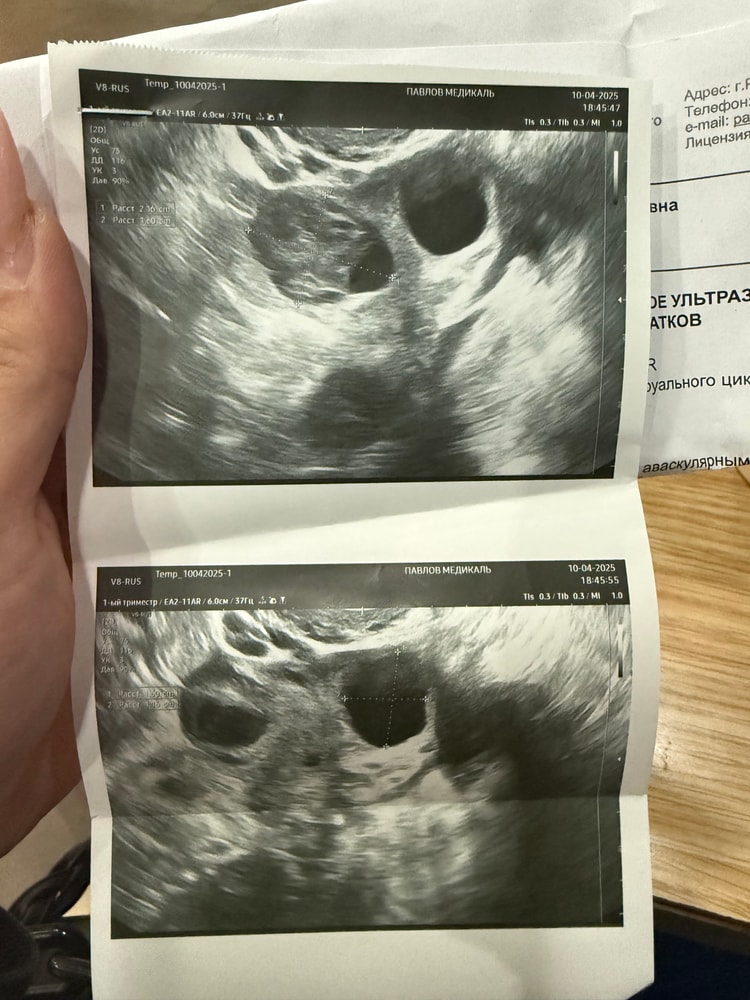

Анастасия в Зачатие 8 месяцев УЗИ УЗИ Всем привет, девочки у кого было такое, делала узи на 20 день цикла, желтое тело 16х16, и еще сделала на 26 день цикла узи появился какой то мешочек рядом, на первом узи не было его, вообщем цикл 28 дне, что это может быть? Посмотрите еще 20 записей на эту тему Отменить Ответить Таня А в заключении, что написано? 11.04.2025 Ответить Овитрель УЗИ на 7 ДПО, кто разбирается, помогите! Чаты Беременных Выберите чат: Январята-2026 Февралята-2026 Мартята-2026 Апрелята-2026 Майчата-2026 Июнята-2026 Июлята-2026 Августята-2026